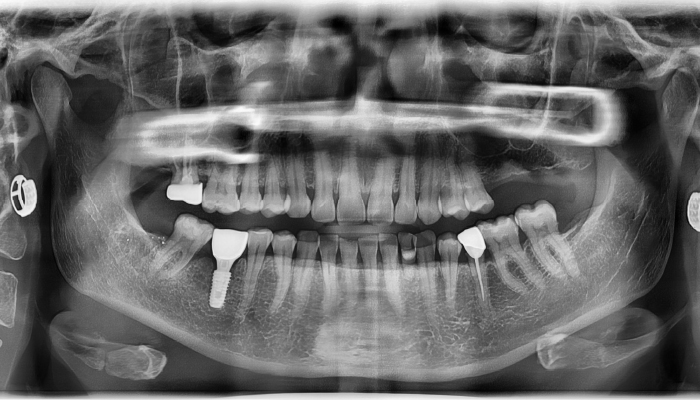

• 식립 전

식립 후